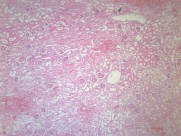

肾小管坏死(12)张

为急肾衰最常见类型,约占75%~80%.它是由于各种病因引起肾缺血及/或肾毒性损害导致肾功能急骤、进行性减退而出现的临床综合征.主要表现为肾小球滤过率明显降低所致的进行性氮质血症,以及肾小管重吸收和排泄功能低下所致的水、电解质和酸碱平衡失调.据尿量减少与否分少尿(无尿)…